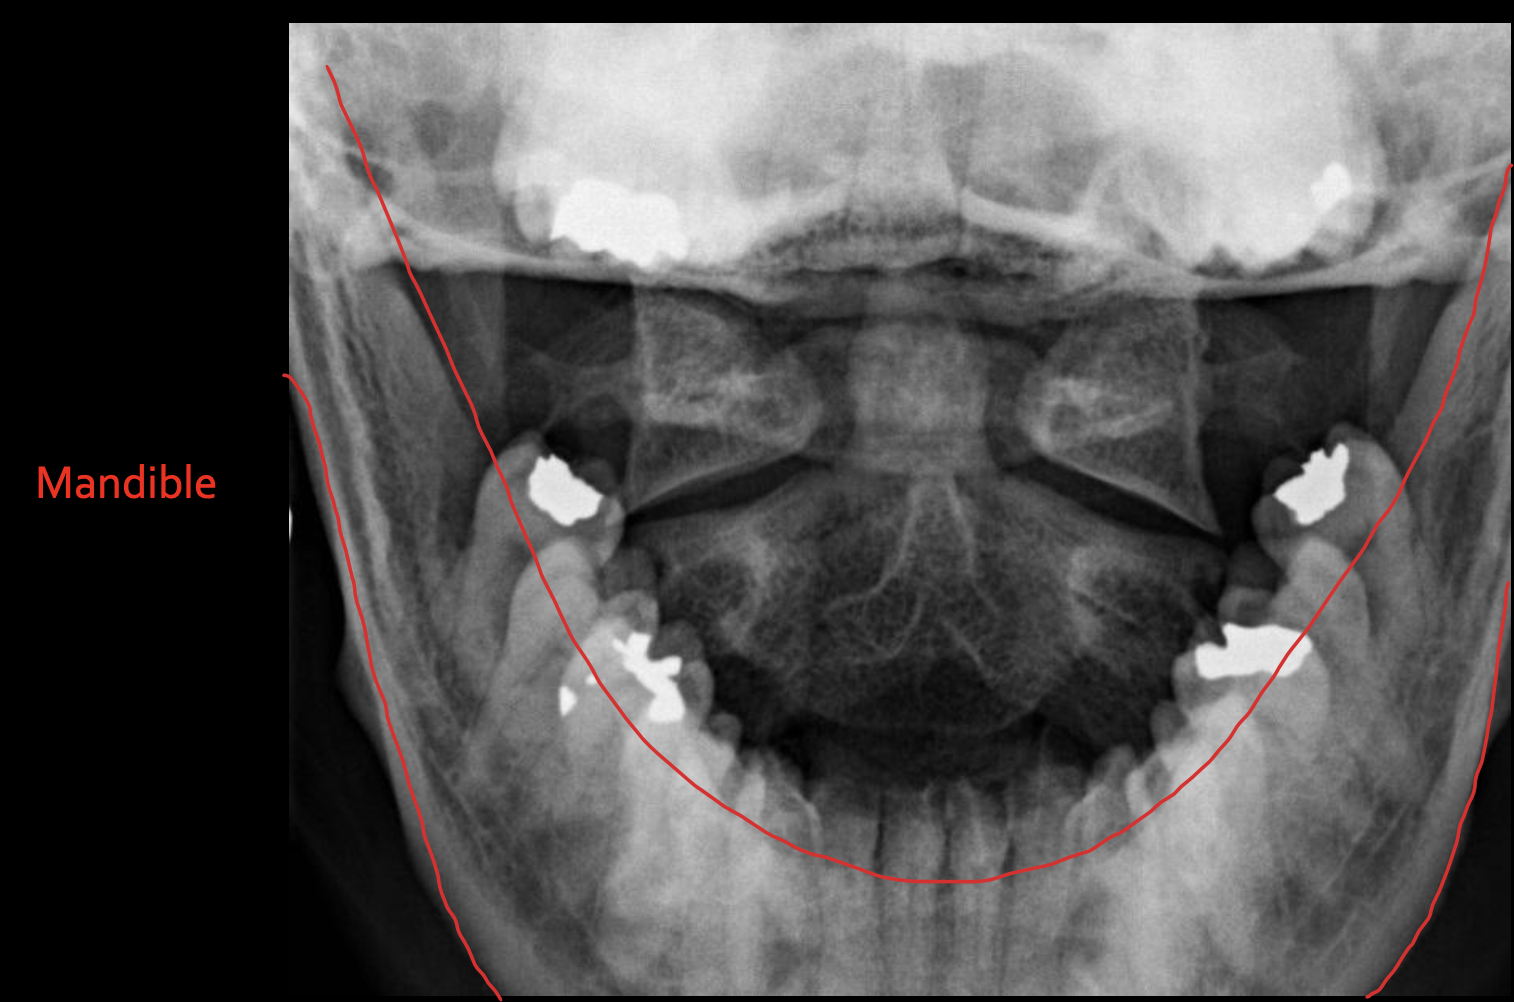

下颌骨

Mandible